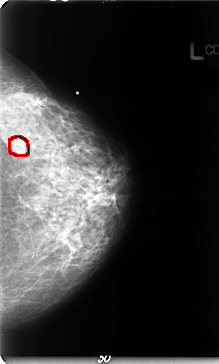

B_3072_1.LEFT_MLO

LEFT_MLO LINES 4656 PIXELS_PER_LINE 3016 BITS_PER_PIXEL 12 RESOLUTION 50 OVERLAY

FILE: B_3072_1.LEFT_MLO.OVERLAY

TOTAL_ABNORMALITIES 1

ABNORMALITY 1

LESION_TYPE MASS SHAPE IRREGULAR MARGINS OBSCURED-ILL_DEFINED

ASSESSMENT 3

SUBTLETY 3

PATHOLOGY MALIGNANT

TOTAL_OUTLINES 1

BOUNDARY